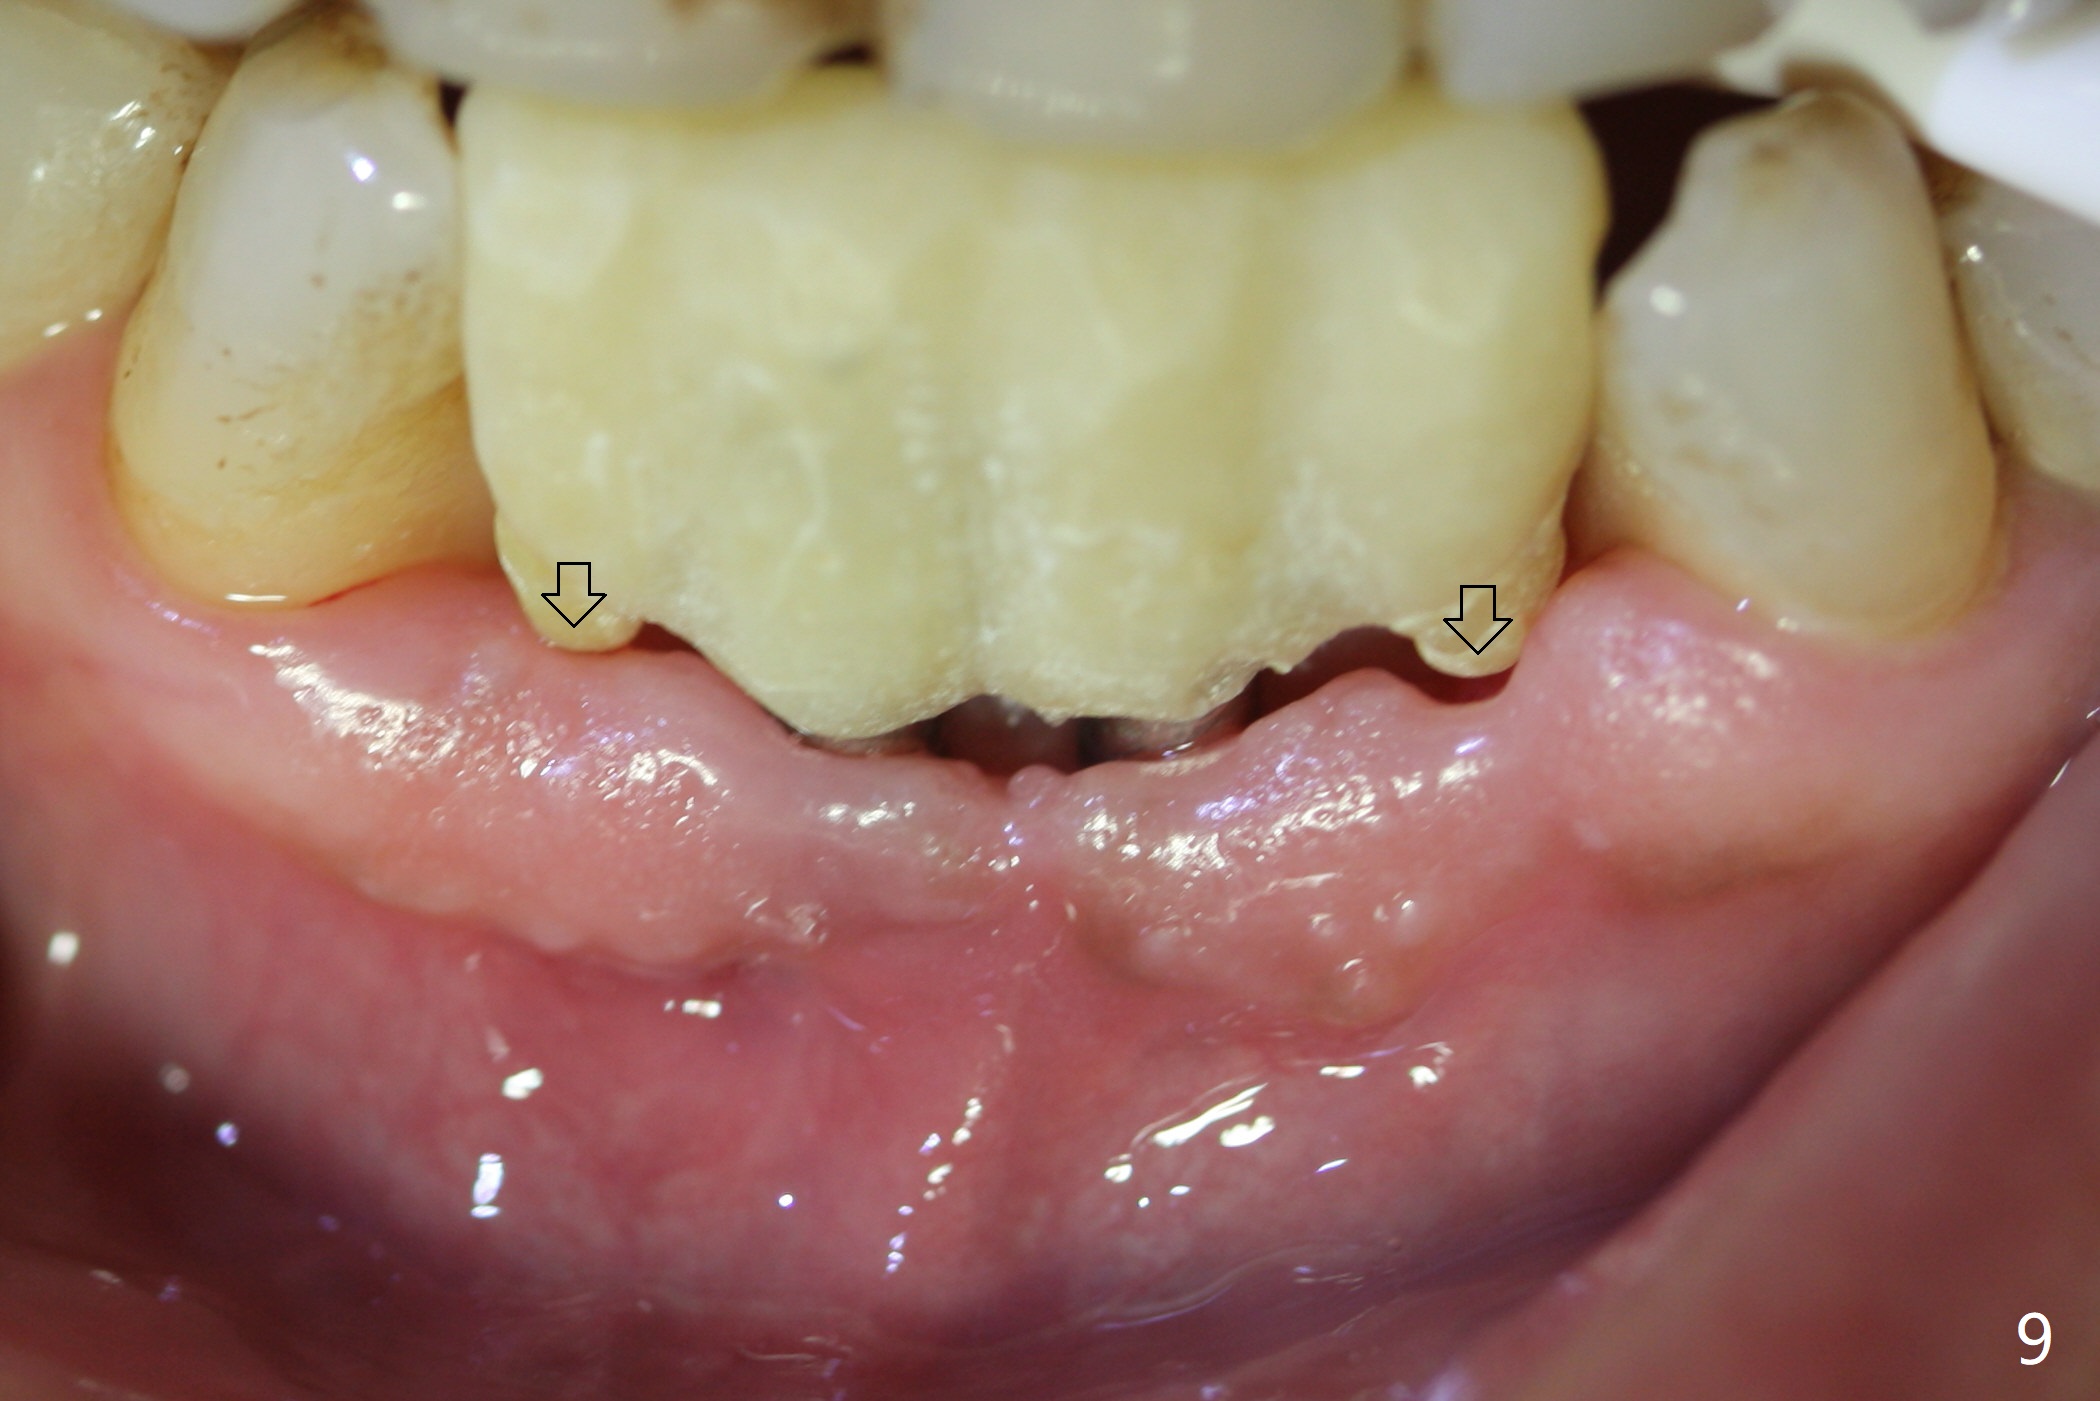

When the patient (smoker) returns for treatment, the apical abscess associated with #25 and 26 reduces with oral Amoxicillin. He agrees with 4 incisor extraction because of 2 apical fistulae (Fig.1 >). Osteotomy starts at the central incisor sockets due to mesial root exposure of the canines (Fig.2 arrowheads) and buccal alveolar bone fracture between #23 and 24 (Fig.7). Two of 3x14(4) mm 1-piece implants are placed with ~ 2 mm buccal gap (Fig.3). After Vanilla graft is placed in the bony defects (Fig.5 *) and Osteogen plug, sutures are placed (Fig.4). The implants are then placed deep to decrease thread exposure (Fig.6). Periodontal dressing is applied instead of provisional. Alveolar bone fracture between #23 and #24 accounts for why an implant is less suitably placed at #24 (Fig.7). Three months postop, composite is added to the pontic areas of the provisional (Fig.8 *). When the provisional is seated, the convex pontics press the used-to-be-flat gingiva (Fig.9 arrows). Thus the concave gingiva forms (Fig.10 *) with corresponding papillae (^). In fact the photos of Fig.8-10 is taken ~3 weeks later. Most of the grafted bone remains in place 3.5 months postop (Fig.11). A piece of floss with 2 knots in one end is placed between the middle units of the final bridge before cementation (Fig.12 (4 months 10 days postop)). In fact removal of residual cement is not so simple. It is tedious (Fig.13,14). An asymptomatic buccal fenetration with implant thread exposure is found 2 months post cementation and persists for another month in spite of advice to reduce smoking (1/2 ppd) and use of water pik (Fig.15). The area will be debrided, followed by bone graft and PRF in a month.